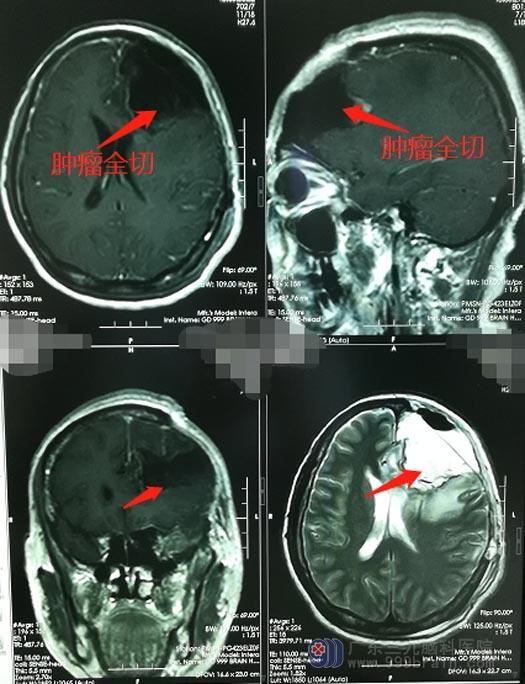

似乎已经听到了死神的敲门声,李阿姨的家人态度非常坚决:尽最大努力拉她一把!李阿姨的手术指征明显,鲁明主任带领外五科团队急诊在全麻下行“左侧额岛叶、左基底节区占位切除术+去骨瓣减压术”,手术顺利,术中出血仅约200ml,未输血。术后复查CT提示术区无出血,中线较前恢复。

术后第二天,李阿姨的意识已经恢复,没有出现继发性的肢体活动障碍;术后病理检查报告:恶性黑色素瘤。